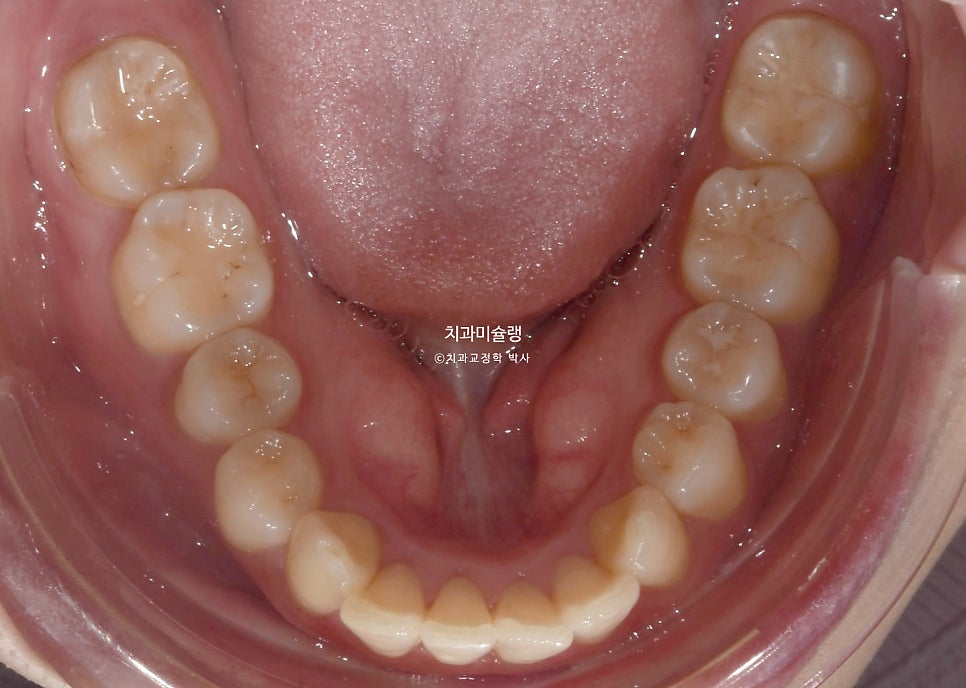

악궁이 좁고 뾰족합니다.

교합은 물샐틈 없이 좋으며 사랑니까지 배열되었습니다.

뽀족했던 악궁모양이 돌출된 앞니가 뒤로 들어가며 둥근 현태가 되었습니다.

작은어금니를 2개 뺐지만, 치아갯수는 14개로 정상입니다. 사랑니가 큰어금니 역할을 하고있기 때문이죠.

사랑니까지 물샐틈 없는 교합을 보입니다.